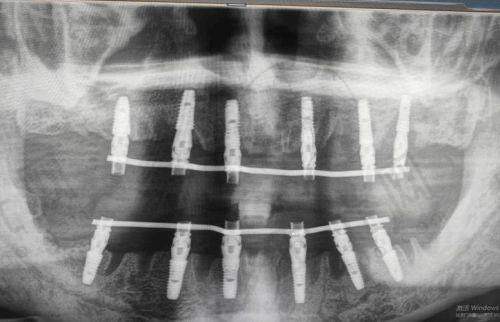

2. 必做准备:要做好全方面的口腔检查,包括X光片、CT等,让医生了解咱们的口腔情况,比如牙槽骨的密度、高度等,以便制定合适的种植方案。同时,要跟医生说清楚自己的病史和过敏史,比如是否有高血压、糖尿病等疾病,是否对某些药物过敏,这关系到手术的安心性。

1. 徐州口腔医院:徐州口腔医院开展多种种植牙技术,像常规种植、all - on - 4、all - on - 6等,技术较为全方面。收费6500元的种植牙在其收费区间内比较适中。虽然医生信息文档未提及,但作为当地有名的口腔医院,技术有一定的保护。而且医院开展的口腔治疗项目丰富,能为咱们提供一站式的口腔服务。

2. 徐州美奥口腔:这是一家正规私立连锁牙科,设有“MCIC复杂病例种植中 心”,擅长微创种植牙,种植体导航技术,all on four全口种植即刻负重,翼板区种植技术。医生团队有汪龙河、窦方伟、惠希琪等。韩国奥齿泰种植牙5500元起/颗,价格和徐州口腔医院6500元的种植牙有一定的可比性。这里种牙技术好,服务便捷,患者体验佳,是徐州牙科医院排名前十。

3. 徐州正博口腔医院:作为二级专科口腔医院,设立了无菌手术室,有着复杂病例种植中 心如穿颧穿翼种植、all - on - 4半口全口即刻种植技术。医生有王勇、李明等。韩国进口种植牙2980元起,韩国美格真种植牙4899元/颗等多种种植牙价格可供选择。以可靠医疗技术和优质服务在淮海经济地区享有较高声誉,设备高端,消毒严格,价格透明。